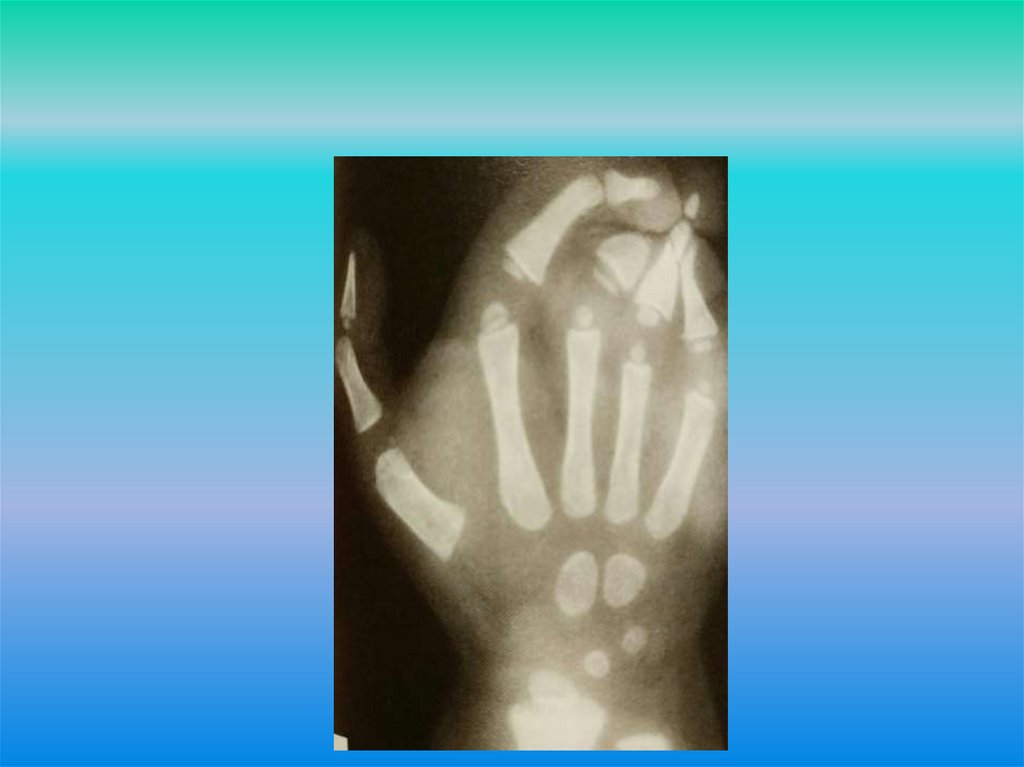

Сложная концевая форма синдактилии

Синдактилия – врожденный порок развития

конечностей, заключающийся в неполном либо

полном сращении двух или более

пальцев кисти/стопы.